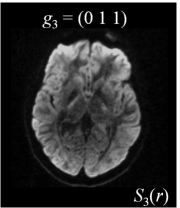

Six axial DW measurements and one non-DW image are shown in Figure 1, along with the corresponding magnetic field gradients . Note the difference in intensity values for different gradient directions.

| (a) | (b) | (c) | (d) |

| (e) | (f) | (g) | (h) |